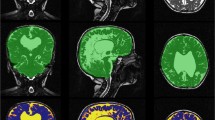

The volume, transformed T2, and difference images were analyzed by a multispectral classification tool which used a feed-forward neural network to segment the background, whole brain, and CSF regions per our previous work [13]. A sample region for each of the three classifications was manually demarcated by the observer, and misclassifications corrected as needed. Only the CSF region required two sample regions, one from a ventricle and another near the edge of the brain. The classifications for the sample slice were reviewed and then propagated for all image slices. In all cases, image segmentation was verified by a board certified neuroradiologist (CH, 14 years experience) and stored for later analysis (Figs. 2 and 3).

Sample normal MRI group segmentation images. Eight-month-old female presenting with anisocoria. a Axial T2 images. b Axial T2 registered EPI images with segmented object regions. c 3D ventricular volume images. Object map colors are green, blue, yellow, magenta, and light blue for brain (722.27 ml), subarachnoid space (65.44 ml), lateral ventricle (10.75 ml), third ventricle (0.64 ml), and fourth ventricle (0.86 ml), respectively.

Sample enlarged subarachnoid spaces of infancy group segmentation images. Twenty-month-old male presenting with macrocephaly and speech delay. a Axial T2 images. b Axial T2 registered EPI images with segmented object regions. c 3D ventricular volume images. Object map colors are green, blue, yellow, magenta, and light blue for brain (1184.99 ml), subarachnoid space (204.46 ml), lateral ventricle (26.45 ml), third ventricle (2.62 ml), and fourth ventricle (1.23 ml), respectively.